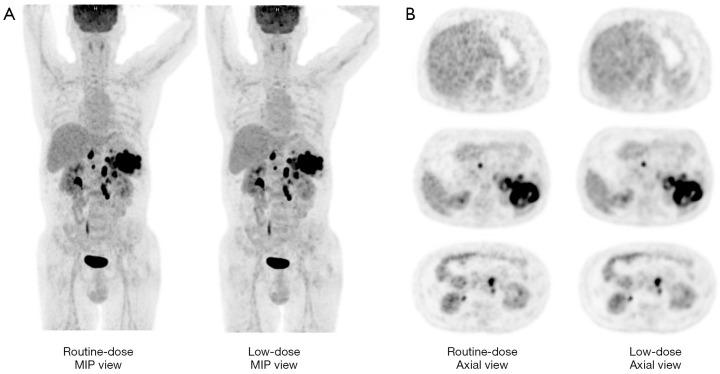

Patients with lymphoma receive multiple positron emission tomography/computed tomography (PET/CT) exams for monitoring of the therapeutic response. With PET imaging, a reduced level of injected fluorine-18 fluorodeoxyglucose ([F]FDG) activity can be administered while maintaining the image quality. In this study, we investigated the efficacy of applying a deep learning (DL) denoising-technique on image quality and the quantification of metabolic parameters and Deauville score (DS) of a low [F]FDG dose PET in patients with lymphoma.

METHODS

This study retrospectively enrolled 62 patients who underwent [F]FDG PET scans. The low-dose (LD) data were simulated by taking a 50% duration of routine-dose (RD) PET list-mode data in the reconstruction, and a U-Net-based denoising neural network was applied to improve the images of LD PET. The visual image quality score (1 = undiagnostic, 5 = excellent) and DS were assessed in all patients by nuclear radiologists. The maximum, mean, and standard deviation (SD) of the standardized uptake value (SUV) in the liver and mediastinum were measured. In addition, lesions in some patients were segmented using a fixed threshold of 2.5, and their SUV, metabolic tumor volume (MTV), and tumor lesion glycolysis (TLG) were measured. The correlation coefficient and limits of agreement between the RD and LD group were analyzed.

RESULTS

The visual image quality of the LD group was improved compared with the RD group. The DS was similar between the RD and LD group, and the negative (DS 1-3) and positive (DS 4-5) results remained unchanged. The correlation coefficients of SUV in the liver, mediastinum, and lesions were all >0.85. The mean differences of SUV and SUV between the RD and LD groups, respectively, were 0.22 [95% confidence interval (CI): -0.19 to 0.64] and 0.02 (95% CI: -0.17 to 0.20) in the liver, 0.13 (95% CI: -0.17 to 0.42) and 0.02 (95% CI: -0.12 to 0.16) in the mediastinum, and -0.75 (95% CI: -3.42 to 1.91), and -0.13 (95% CI: -0.57 to 0.31) in lesions. The mean differences in MTV and TLG were 0.85 (95% CI: -2.27 to 3.98) and 4.06 (95% CI: -20.53 to 28.64) between the RD and LD groups.

CONCLUSIONS

The DL denoising technique enables accurate tumor assessment and quantification with LD [F]FDG PET imaging in patients with lymphoma.